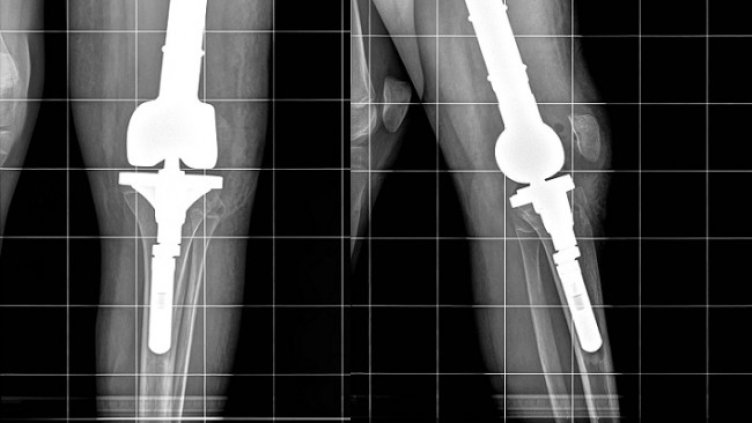

Две седмици след уникалната операция Райна от Пловдивско може отново да ходи с двата си крака. Момичето постъпва в ортопедичната болница със страховитата диагноза Сарком на Юинг, обхващащ лявото бедро по цялото протежение. След проведена предоперативна химиотерапия в Детската онкохематология в Пловдив екип на Клиниката по ортопедия извършва премахване на тумора с цялата бедрена кост и заместване на дефекта с модулна мега-протеза, включваща бедрено стебло, ендопротези на тазобедрената и коленната стави, разказаха от болницата.

"Отстранихме цялата бедрена кост и извършихме реконструкция с туморна модулна ендопротеза, изработена в Германия, обяснява д-р Патриков. Протезата е бутикова, поръчана и изработена, съобразно размерите на костите на пациентката. Тази модулност позволява и по-късно във времето при необходимост да се подменят модулите. Защото пациентката е на 13 години и се предполага, че има още 1-2 години растеж на костта. Така че, ако в процеса на израстване оперираният крак изостане по дължина от другия, ще има възможност да бъде уеднаквен с подмяна на един от поставените по средата модули", обясни лекарят.